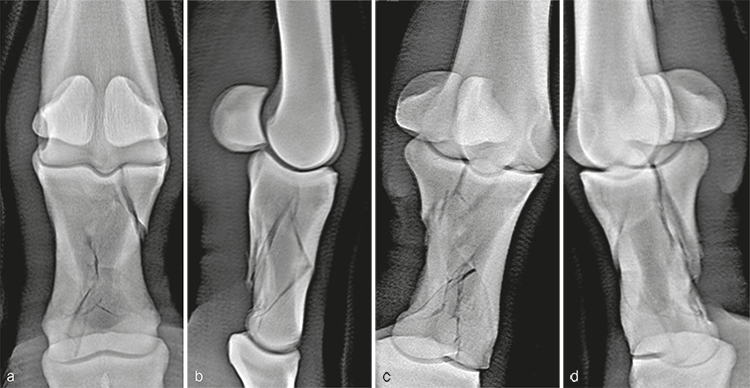

Radiographic evaluation at the time of admission confirmed the highly comminuted fracture configuration and revealed considerable collapse of P1 with malalignment and overriding of the fracture fragments (Fig 3). Due to the highly unstable nature of the injury and the presence of multiple sharp fracture fragments, the immediate concern was the potential for skin penetration and conversion to an open fracture. Consequently, the mare was placed under general anesthesia to facilitate indirect fracture reduction through traction on the distal limb. Once alignment was confirmed radiographically, the distal limb was stabilized by application of a fiberglass cast extending distally from the proximal metacarpus and incorporating the hoof.

A 10-year-old French warmblood gelding weighing 580 kg was presented a few hours after developing a severe left forelimb lameness following an unwitnessed paddock injury. Initial radiographs demonstrated a severely comminuted, minimally displaced fracture of P1 (Fig 7). The distal limb was immediately placed in a fiberglass cast by the referring veterinarian before transporting the horse, which prevented further displacement of the fragments.